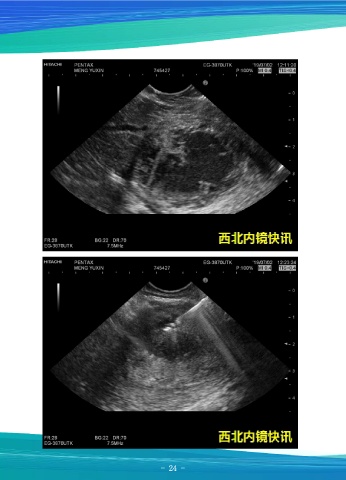

胰腺穿刺物病理检查结果(C2019-2372)镜下可见散在淋巴细胞及少量中性粒细

胞,并见少数组织细胞,包浆内含棕黄色颗粒,提示陈旧性出血改变。患者无腹痛腹胀

等不适症状后,出院观察。